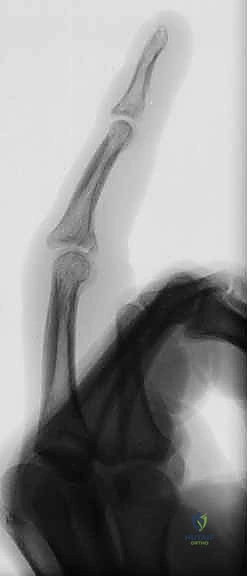

Figure 1A demonstrates a typical, more severe dorsal fracture-dislocation, involving approximately 65% of the volar articular surface.

Figures 1B and 1C illustrate proximal interphalangeal joint volar dislocations.

Figures 1D and 1E depict proximal interphalangeal joint pilon fractures.